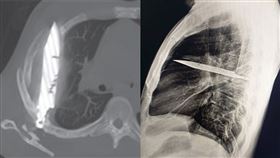

44歲男乳頭流膿 X光驚見「刀插胸腔8年」

國外一名44歲男子因為「乳頭流膿」到醫院就診,然而除...